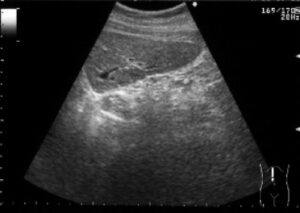

最近は、ご自分で妊娠反応を確かめてみえるかたも多いですが、妊娠の確定診断には超音波検査が必要です。妊娠反応の感度がとてもよくなったため、妊娠反応がでても超音波で赤ちゃんをいれている袋が見えない時期というのが数日から1週間程度あります。妊娠週数の計算法は、生理がはじまって14日目に排卵がおこっていることを前提としているため、超音波で赤ちゃんが見えない場合には、「実際に排卵したのは14日目よりも遅く、病院にくるのがはやかったのでみえない」「妊娠は成立したが、何らかの理由で正常に進行していない」「異所性(子宮外妊娠)」の3つの場合があります。

妊娠週数は最後の生理が始まった日から数えて280日目を分娩予定日とし、週数で数えます。28日周期で生理が合っている方だと、4週0日が次の生理の予定の日となります。 おおむね5-6週で、赤ちゃんのはいっている袋(胎嚢)がみえてきます。赤ちゃんの心拍がみえるようになるのが7週前後です。8週から11週にかけての赤ちゃんの大きさを計測して、生理から計算した分娩予定日とのずれが大きければ予定日を修正します。そしてその後は母子手帳をお渡しして、いわゆる妊婦健診を開始します。